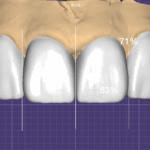

3.1 Diagnostic Wax-up: 실패를 방지하는 설계도

[사진 2 참조] 저는 환자의 구강 스캔 데이터와 안면 사진을 매칭하여 디지털 왁스업을 먼저 시행합니다. 이후 이를 실물 모델로 제작하여 환자의 입술 라인(Lip Line)과 저작 시의 간섭 여부를 확인합니다.

- Prescription(처방): 기공사에게 단순히 “예쁘게”를 요구하지 않습니다. “중절치 대비 측절치의 폭경 비를 조정하고, 절단연의 투명층은 1.5mm로 설정할 것”과 같은 수치 기반의 처방을 내립니다.